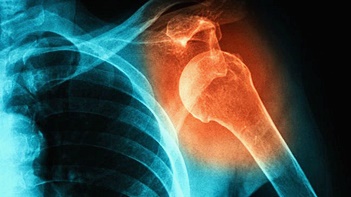

어깨 탈구 증상 3가지

사람의 어깨는 몸통에서 팔로 이어지는 부분을 말합니다. 이는 겨드랑이, 가슴, 세모근부 어깨뼈, 목뒤 까지를 말하는데요. 어깨는 손을 사용하기 편한 위치로 이동시키는 역할을 하기 때문에 상당히 중요한 부위 중 하나입니다. 어깨 탈구는 어깨 관절이 정상 위치에서 이탈한 상태를 말하는데요.

완전하게 벗어나는 경우를 완전 탈구, 관절의 일부를 접촉하고 있는 경우를 이탈구라고 합니다. 탈구는 선천성 탈구와 후천성 탈구로 나누어지며 고관절 탈구가 대표적입니다.